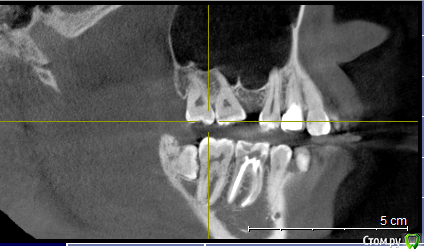

Naliy Опубликовано 2 июля, 2020 Поделиться Опубликовано 2 июля, 2020 Добрый день!Мне 24 года. Два года назад из-за неправильного лечения и пломбирования пришлось удалить шестой зуб сверху (правая сторона). В настоящее время началась рецессия десны на верхнем левом клыке, и стоматолог полагает, что это связано с неравномерной нагрузкой на челюсть из-за отсутствия зуба, поэтому советует ортодонтическое лечение.За 2 года 7 и 8 зубы сдвинулись и оставили 4-5 мм от пустого места 6 зуба. Прикус дистальный; по словам одного ортодонта, зубы с правой стороны смыкаются более-менее правильно, а с левой - нет. На зубах есть меловидные пятна, есть пломбы.Побывала у трех ортодонтов, но мнения у них расходятся немного:1) удалить зубы мудрости, освободить место под имплант;2) удалить один зуб мудрости с верхней челюсти, передвинуть 7 и 8;3) удалить один зуб мудрости и один 4 зуб слева и сдвинуть 7 - 8. Имплантолог сказал, что кость в районе 6 зуба тонкая, а ортодонтическое лечение неизбежно,т.к. мало места для импланта. Подскажите, как лучше решить проблему отсутствующего зуба?1. Можно ли передвинуть 7 и 8 на место 6? Высока ли вероятность неудачного исхода? 2. Необходимо ли удалять 4 зуб для выравнивания зубного ряда? Врач может определить необходимость удаления зуба только с помощью специальных расчетов или КТ и очного осмотра достаточно?3. Обязательно ли носить брекеты на нижней челюсти? Можно ли попробовать их выпрямить трейнерами, т.к. полноценное лечение очень трудно в финансовом плане. Поэтому я надеюсь или на лечение на обеих челюстях с передвижением 7-8 зубов, или на лечение верхней челюсти с последующей имплантацией. Буду благодарна за вашу помощь. Ссылка на комментарий

Дмитрий Л. Опубликовано 3 июля, 2020 Поделиться Опубликовано 3 июля, 2020 Нужно комплексное ортодонтическое лечение. Удалить верхнюю 8, отодвинуть 7 и поставить имплант в позицию 6. Трейнеры неэффективны. Рецессия на левом клыке с отсутствующим зубом не связана. Побывала у трех ортодонтов, но мнения у них расходятся немного:1) удалить зубы мудрости, освободить место под имплант;2) удалить один зуб мудрости с верхней челюсти, передвинуть 7 и 8;3) удалить один зуб мудрости и один 4 зуб слева и сдвинуть 7 - 8.Видимо вы запутались немного и неправильно поняли докторов. Ссылка на комментарий

Naliy Опубликовано 3 июля, 2020 Автор Поделиться Опубликовано 3 июля, 2020 Дмитрий, спасибо, что откликнулись на тему!Я не очень понимаю, почему Вам кажется, что я неверно восприняла слова докторов. Пишу чуть подробнее их ответы:1. Удалить оба зуба мудрости с верхней челюсти, передвинуть назад седьмой зуб и освободить место под имплант.2. Удалить один зуб мудрости (с левой стороны), а правый зуб мудрости и седьмой передвинуть на место удаленного.3. Удалить один зуб мудрости (с левой стороны) и четвертый зуб (с левой стороны), чтобы было пространство для выравнивания зубного ряда и освободить место для второго левого зуба; передвинуть правый зуб мудрости и семерку на место удаленного. Подскажите, почему по Вашему мнению нужно делать именно имплантацию, а не передвижение зубов? Вы не могли бы подсказать к какому специалисту нужно обратиться для выявления причины рецессии и ее устранения? Полное ортодонтическое лечение я не могу себе позволить из-за высокой стоимости, поэтому не могу рассматривать вариант брекетов на две челюсти и последующей имплантации, плюс судя по словам имплантолога возможно понадобиться восстановление костной ткани. Ссылка на комментарий